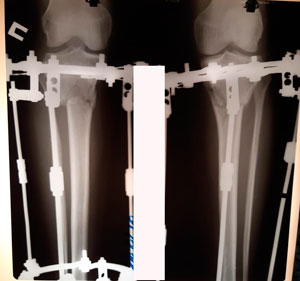

Рентген перед фиксацией

Вложения

IMG_8197-12-01-20-08-07.JPG

IMG_8196-12-01-20-08-07.JPG